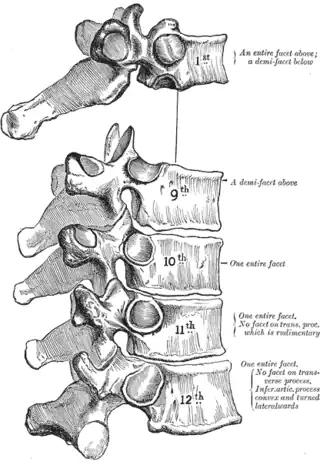

The first thoracic vertebra has, on either side of the body, an entire articular facet for the head of the first rib, and a demi-facet for the upper half of the head of the second rib.

The ninth thoracic vertebra may have no demi-facets below. In some subjects however, it has two demi-facets on either side; when this occurs the tenth doesn't have facets but demi-facets at the upper part.

The tenth thoracic vertebra has an entire articular facet (not demi-facet) on either side, which is placed partly on the lateral surface of the pedicle. It doesn't have any kind of facet below, because the following ribs only have one facet on their heads.

In the eleventh thoracic vertebra the body approaches in its form and size to that of the lumbar vertebrae.

The articular facets for the heads of the ribs are of medium size, and placed chiefly on the pedicles, which are thicker and stronger in this and the next vertebra than in any other part of the thoracic region.

The spinous process is short, and nearly horizontal in direction.

The transverse processes are very short, tuberculated at their extremities, and do not have articular facets.

The twelfth thoracic vertebra has the same general characteristics as the eleventh, but may be distinguished from it by its inferior articular surfaces being convex and directed lateralward, like those of the lumbar vertebrae; by the general form of the body, laminae, and spinous process, in which it resembles the lumbar vertebrae; and by each transverse process being subdivided into three elevations, the superior, inferior, and lateral tubercles: the superior and inferior correspond to the mammillary and accessory processes of the lumbar vertebrae. Traces of similar elevations are found on the transverse processes of the tenth and eleventh thoracic vertebrae.